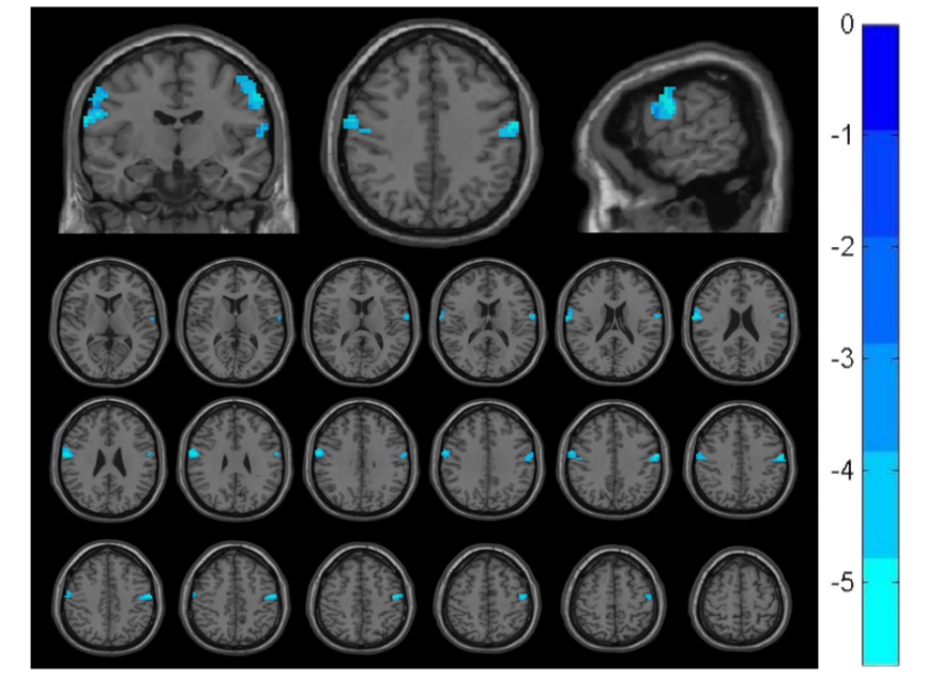

The altered brain regions in patients with chronic pain before and after stimulation included postcentral and precentral gyrus (P<0.001)[figure2], while in patients with no pain only included the middle temporal gyrus (P<0.001)[figure3].

ReHo Changes in Pain Group Pre/Post-Stimulation